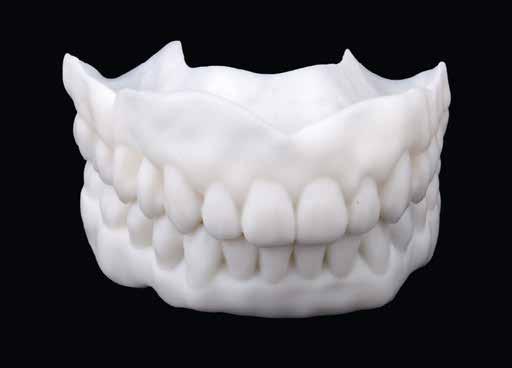

A biológiai orvoslás a pácienst helyezi a középpontba a mindenkori fogorvosi és fogtechnikai eljárások és az azokból képzett konzekvenciák vonatkozásában. Időközben már bizonyított tény, hogy az emberi testbe helyezett fém jelenléte a legrövidebb időn belül a vérképben is kimutatható. Éppen ebben rejlenek a fogászatban, különösen az implantológiában nagy veszélyek. Mert ha még olyan nagy értékűek is a felhasznált anyagok, akkor is találhatók a tiszta titán felszínén is mikroszennyeződések. A fémek oldódhatnak a nyálban, lenyelhetők, a későbbiekben megváltoztathatják sejtjeink szerkezetét, ami elviselhetetlenséghez, autoimmun betegséghez vezethet. Dr. Dr. Michael Rak Bernriedből, illetve az augsburgi Highfield/Design cég Norbert Wichnalek vezette fogtechnikuscsoportja kifejlesztett egy olyan eljárásmódot, ami felel ezekre a kihívásokra, és a lehető legkevésbé terhelő módon látja el a pácienseket.

Dr. Dr. Michael Rak rendelőjében nem csak üres szó, hogy az ember áll a fogászati történések központjában. Minden a biológiai fogorvoslás terápiája körül forog. Az augsburgi Highfield/Design cég Norbert Wichnalek vezette fogtechnikuscsoportja évek óta foglalkozik a páciensek fémmentes megoldásokkal történő ellátásával. Ezeket erősítették Dr. Dirk Duddeck berlini CleanImplant Alapítványának tanulmányai is. Dr. Duddeck szerint sem a CE tanúsítvány, sem a mégoly neves és nagy gyártó sem tudja garantálni, hogy az implantátumokon ne legyen idegen részecske. Majd 15 éve vizsgál steril csomagolású implantátumokat pásztázó elektronmikroszkóppal. Ezalatt 300 különböző implantátumot vizsgált 200 gyártótól, alaposan analizálva azokat. A 2017 és 2019 közötti vizsgálat, amelyet a berlini Charité Egyetemmel együttműködésben folytatott, megmutatta, hogy szinte minden harmadik, tiszta környezetben kicsomagolt és PEM vizsgálatnak alávetett implantátumminta jelentős szennyezéseket tartalmaz. A steril implantátumfelszínen vas, króm, molibdén, réz, ón, volfrám és nikkel, valamint szerves szenynyeződés is kimutatható volt, még műanyagok jelenléte is. A szennyeződések az implantátumfelszínen, különösen a szerves anyagok jelenléte a gyártási és csomagolási eljárás alatt azt a gyanút ébresztik, hogy fennáll a dentális implantátum nem megfelelő csontosodásának veszélye, illetve felelős lehet a korai csontosodási fázis csontveszteségéért is. 2017 óta a CleanImplant Alapítvány bevezetett egy nemzetközileg elismert vizsgálati eljárást, aminek eredményeképpen a tiszta felszín és megfelelő klinikai dokumentáció esetén elérhető a „Trusted Quality Mark” (megbízható, minőségi gyártmány – a ford.) kitüntetés. Néhány hónap alatt több mint 125 ezer fogorvos csatlakozott a Facebook-on a CleanImplant Alapítvány minőségi kezdeményezéséhez. Azóta is havonta több mint ezer felhasználó keres megbízható információkat a nem terhelő implantátumrendszerekről a projekt honlapján. Az itt bemutatásra kerülő pácienseset megoldása során a szintén

„Trusted Quality Mark”-kal kitüntetett SDS implantátumokat használták – nem véletlenül – Dr. Dr. Michael Rak rendelőjében. A szerzők még egy lépéssel tovább mentek, és a kezelés neuralgikus pontjain a plazmakezelést is alkalmazták.

Az eset

A 75 éves páciens új fogsorokat szeretett volna. Felül nem kielégítő teljes lemezes kivehető fogsora volt, alul pedig szintén nem megfelelő részleges fogsora, néhány devitális, apikális oszteolízist és masszív szekunderkárieszt felmutató mutató maradék frontfogon. Az endodonciai beavatkozást a páciens elutasította. Ehelyett kerámiaimplantátumokra alapozott kezelést kívánt. Az úr általános egészségi állapotában panaszok mutatkoztak. A CMD-index nem volt számottevő. A DVT-vizsgálat (1. kép) alapján megállapítható a 42-es fog decens apikális oszteolízise, számottevő vertikális és horizontális csontveszteség a rágóterületen, valamint az

1. kép: Kiindulási helyzet: az OPG hat devitalizált alsó frontfogat ábrázol, részleges apikális oszteolízissel, szekunderkáriesszel, horizontális csontfelszívódással a rágóterületen.

2. kép: 6 egyrészes SDS kerámiaimplantátum azonnal behelyezve az extrakciót követően.

3. kép: A laborkészítésű formát felhasználva alakították ki az ideiglenest.

4. kép: Kontrollfelvétel: a posztoperatív helyzet az ideiglenessel a hat implantátumon.

FDOK/NICO értelmében HU alapján mért erőteljes csontsűrűség-csökkenés mutatkozik az 18, 17, 13, 23, 27 és 28 fogak régiójában.

Terápia és implantáció

Az operatív beavatkozás előtt a behelyezett fogsorokkal és azok nélkül is beszkennelték az intraorális szituációt, valamint elkészítették a fogsorok digitális másolatát. Ezután óvatosan kihúzták a maradék fogakat, és mindent előkészítettek az azonnali implantációhoz, amelynek során 6 egyrészes SDS kerámiaimplantátumot terveztek behelyezni a meglévő alveolusba a 34-43 közötti területre. Közvetlenül a behelyezést megelőzően a szék mellett még egyszer megtisztították Diener Denta Plas plazmakészülékkel (lásd 49. kép) az implantátumokat, a lehető legteljesebb csírátlanítás – így a páciens csíraterhelésének minimalizálása – érdekében (2. kép) Az alveolus ózonos tisztítását követően behelyezték a hat egyrészes SDS kerámia-implantátumot, A-PRF (saját vérlemezkében gazdag – a ford.) membránokkal megsegítve. A laborkészítésű előre mintázott elemek alapján azonnali ide-

iglenes került az implantátumokra (3. kép), majd röntgennel újólag ellenőrizték a létrejött helyzetet (4. kép)